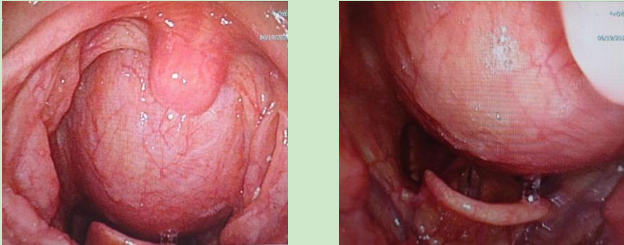

入院后耳鼻咽喉科咽喉头颈组团队立即为其安排详细的术前检查。电子鼻咽喉镜结果提示自鼻咽后壁至下咽后壁约双侧披裂平面见黏膜下巨大光滑隆起,肿物向前膨隆,遮挡部分喉口,口咽及下咽腔前后径狭窄。颈部核磁提示咽后间隙-左侧颈动脉间隙脂肪瘤。综合上述检查结果,初步考虑患者为“咽后间隙-颈动脉间隙巨大脂肪瘤”,手术切除是首选治疗方案。

6月21日,麻醉科瞿敏副主任为患者实施全身麻醉,麻醉时见口咽部后壁隆起较为明显,声门暴露有一定困难,经耐心调整插管角度后,顺利完成经口气管插管。手术由代保强主任主刀,裴达主治医师、耿珊珊主治医师配合。首先使用开口器暴露口咽部,见肿瘤向咽腔膨隆,取咽后壁正中纵行切口,长约5cm,切开咽部黏膜后暴露肿物,见肿物有被膜,探查后发现其背面及侧缘与椎前颈长肌粘连较重。于0°及70°内镜辅助下沿肿瘤被膜钝性分离并联合应用低温等离子刀分离并切断肿物背膜与椎前肌肉的粘连带,完整切除肿物。见肿物呈淡黄色分叶状,表面光滑,大小约11.0cm×5.5cm×3.0cm,检查术腔无肿物残留,无活动性出血点,放置引流管1枚,逐层对位缝合咽后壁肌肉及黏膜。术后病理证实为纤维脂肪瘤。